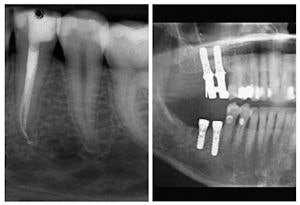

The American Academy of Implant Dentistry and the American Association of Endodontists disagree about whether implants are superior to endodontics. Image courtesy of the AAE. |